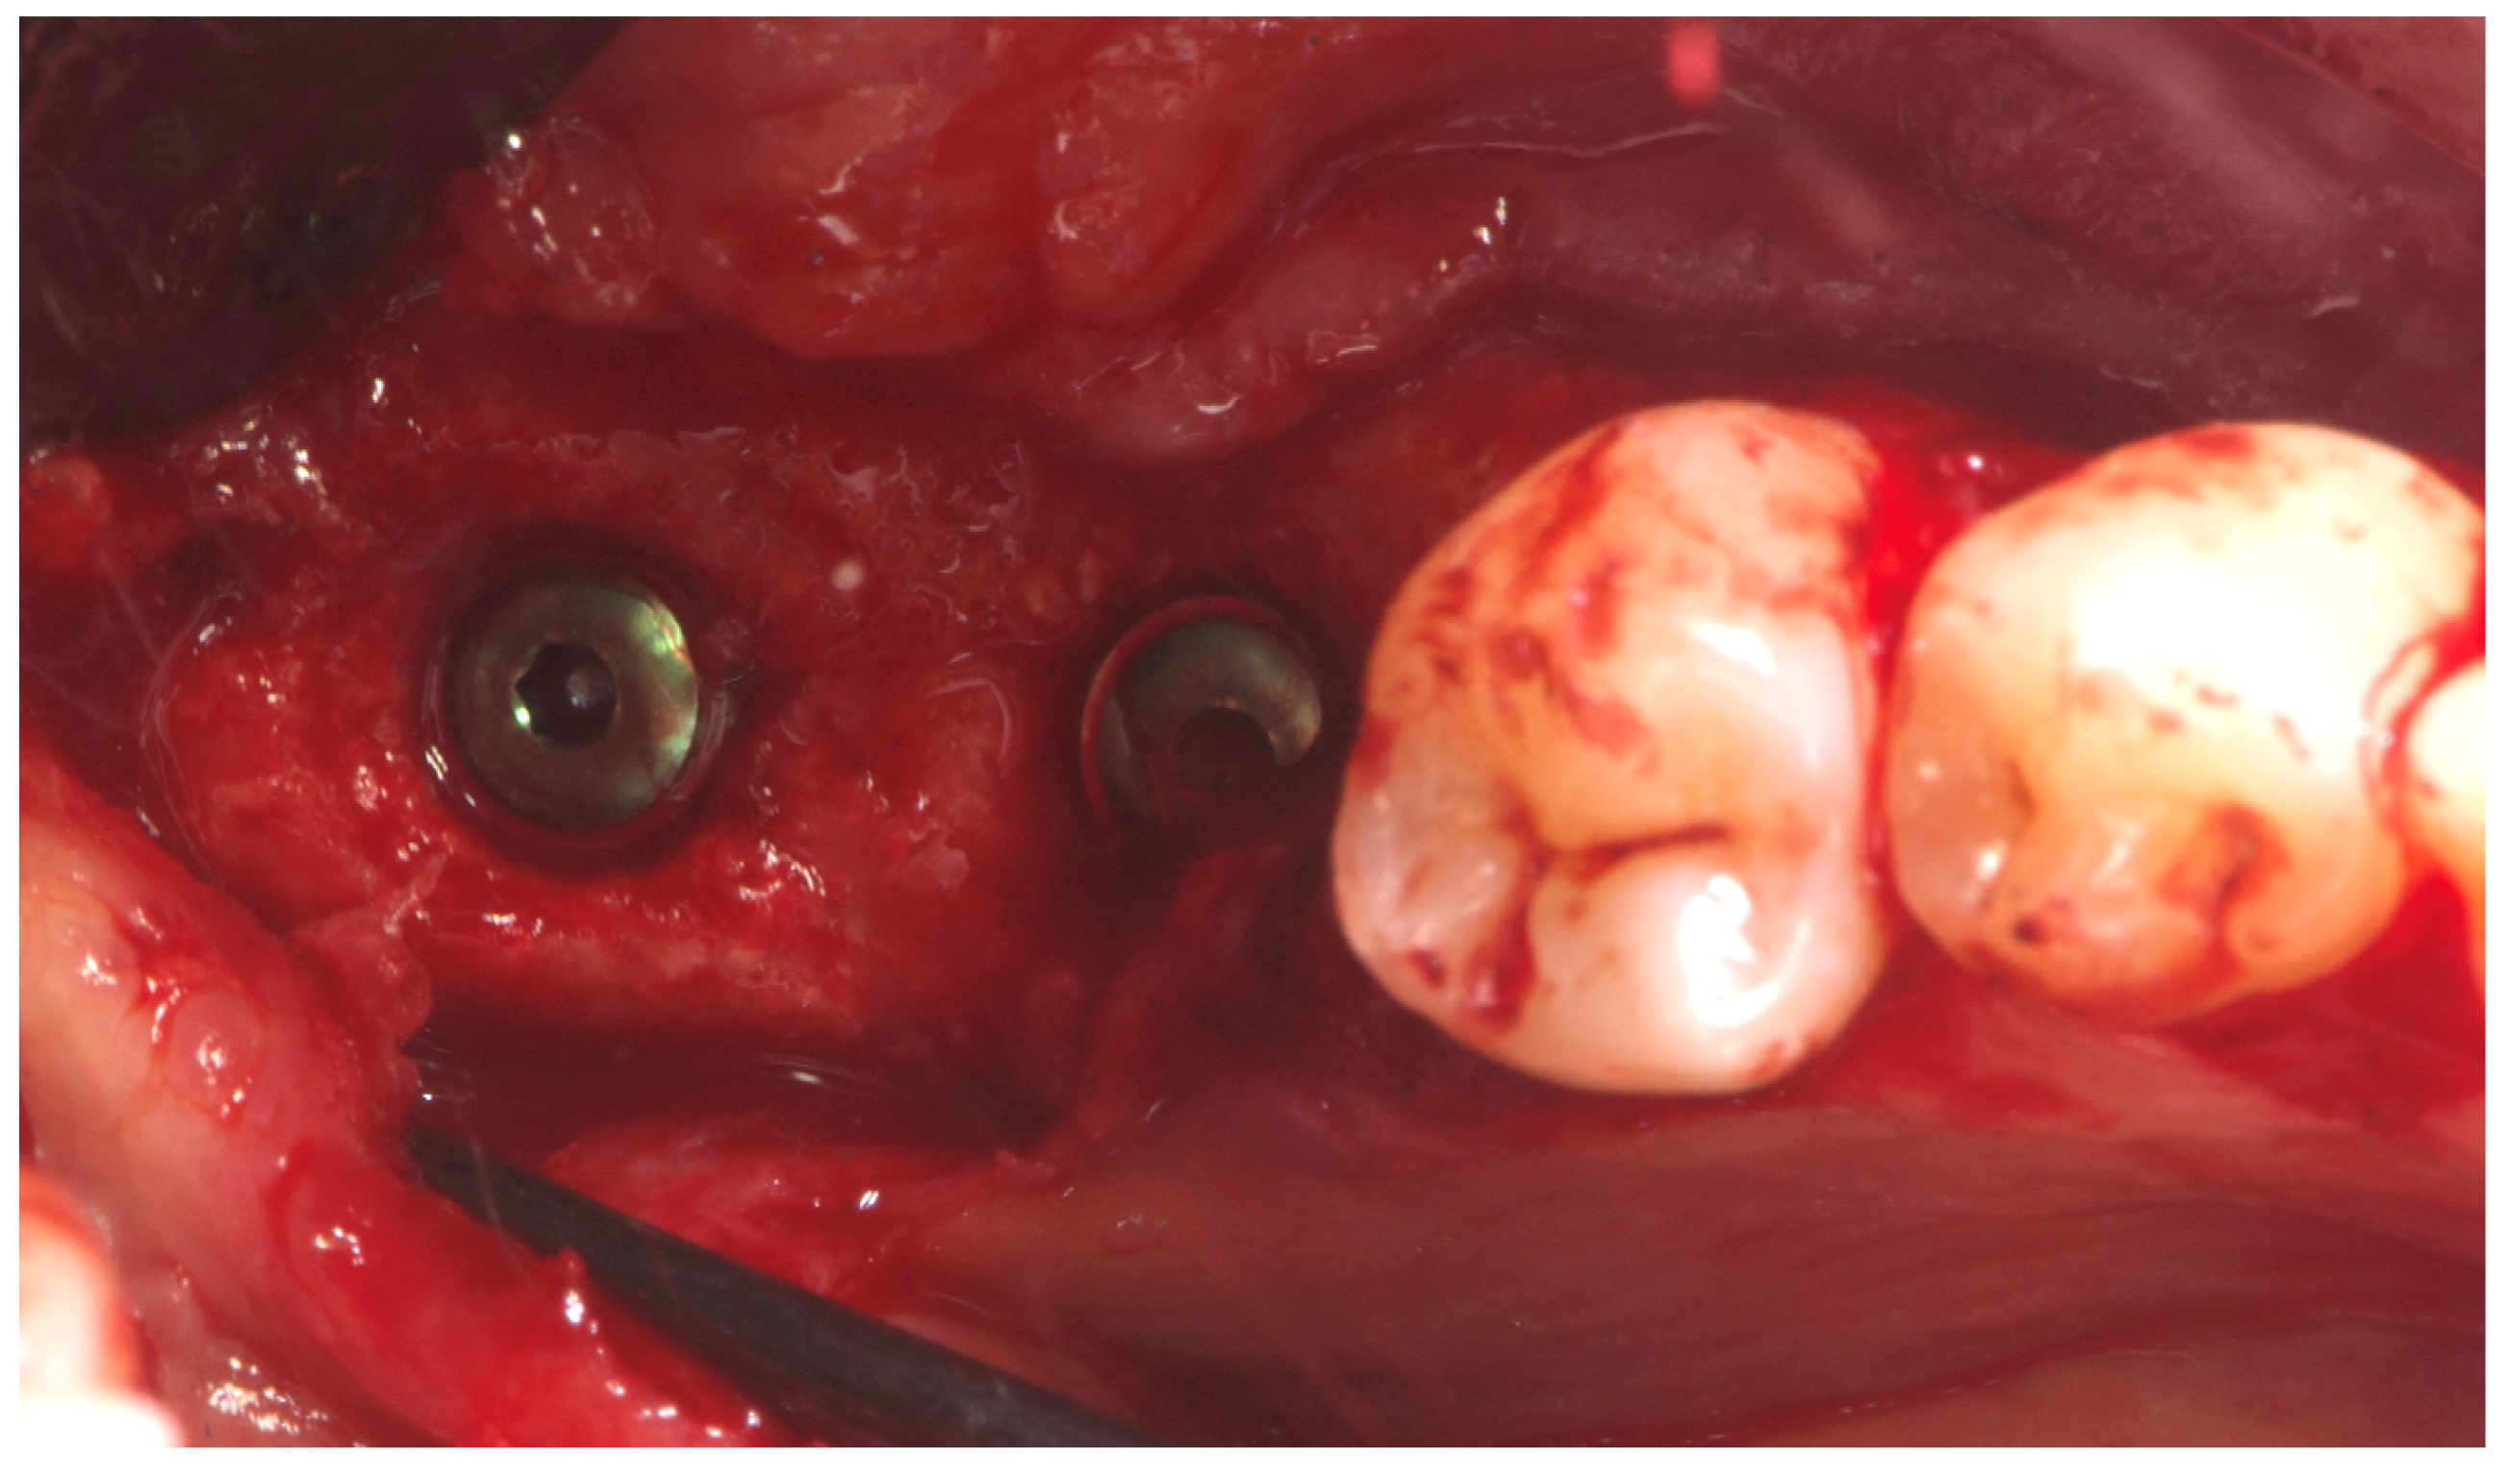

2. Case Summary